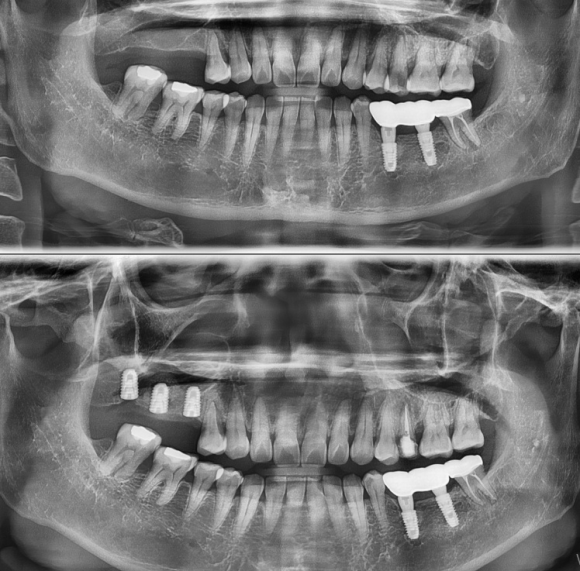

식당을 운영하시는 분입니다. 어금니가 상실된지 너무 오래되어

잇몸뼈가 자연적으로 많이 소실되어 뼈가 좁고 높이도 거의 남아있지 않았기 때문에

3개 임플란트를 심으면서

Ridge split, 상악동수술, 뼈이식 그리고 치조골 확장술을 동반한 임플란트를 식립하게 되었습니다.

입이 많이 벌어지지 않았지만

성공적으로 상악동막의 천공 없이 수술을 마쳤습니다.

총 걸린 시간은 15~20분입니다.